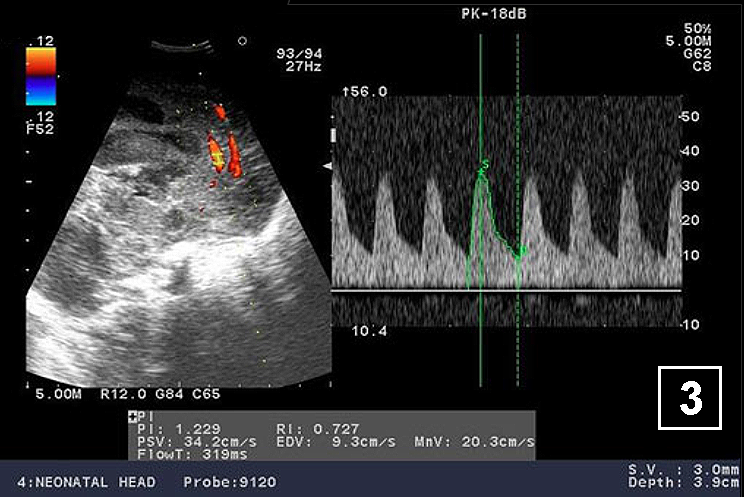

Neonatology Hydrocephalus Doppler 3 Image